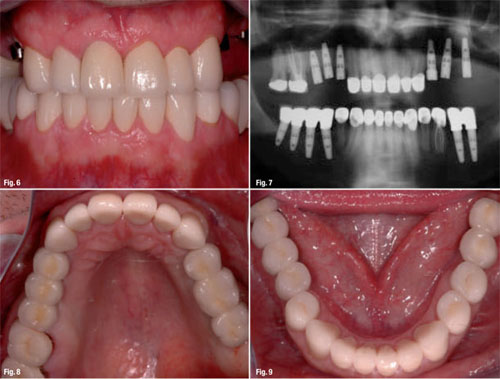

Chuyên gia nha khoa sẽ yêu cầu mình chụp phim CT 3 chiều để kiểm soát mật độ xương, chiều cao của xương hàm có thích hợp để đặt implant hay không. Đó là điều quan trọng trong việc chẩn đoán và lên chiến dịch cấy ghép kết quả. Sau đấy chuyên gia nha khoa sẽ mô tả trên phim để bạn hiểu implant cần đặt ở nơi nào, chiến dịch chữa trị của mình tiếp tới thế nào.

Hình ảnh phim chụp trong quy trình cấy ghép răng Implant